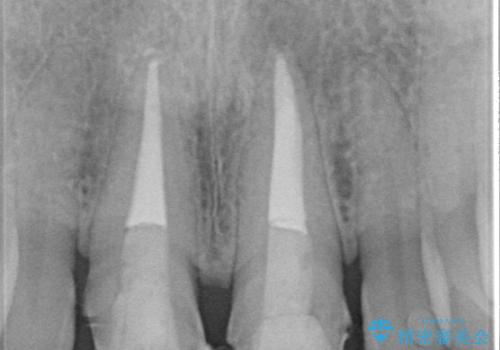

前歯に違和感や根尖病巣(根の先に細菌が溜まっている)が認められたため、治療をご提案しました。

根管治療について

根管治療は歯内の治療なので患者様には見えない場所ですが、ここが細菌で汚染されると激しい痛みや長引く違和感の原因になります。

当院では、清潔な治療を徹底し、顕微鏡を使用した精密な治療を行っています。